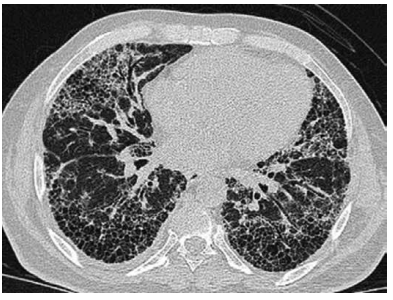

Um homem de 57 anos de idade, tabagista com

35 anos/maço, apresentou quadro de dispneia durante

realização de esforços, com evolução progressiva nos

últimos meses. A tomografia computadorizada de tórax

está disponibilizada a seguir